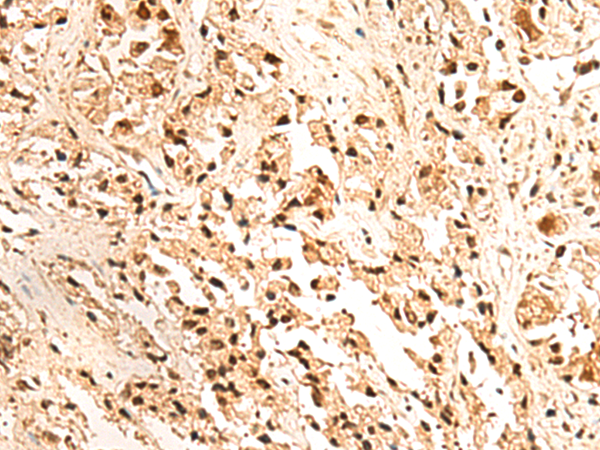

分类: 科研抗体货号: P09868别名: HPRT; HGPRT应用: WB,IHC反应种属: Human, Mouse, Rat